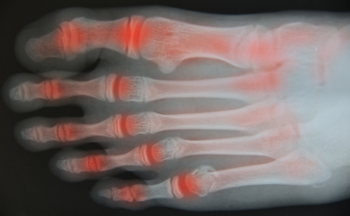

Early onset rheumatoid arthritis is an inflammatory condition that can affect the joints sooner than expected, sometimes beginning in young adulthood or even earlier. It occurs when the immune system mistakenly targets joint tissue, leading to pain, swelling, stiffness, and warmth. The feet and ankles are often among the first areas involved, which can make walking uncomfortable and limit daily activity. Symptoms may come and go at first, but without care, joint changes can become more persistent over time. Early evaluation is important to identify the condition and begin treatment that helps control inflammation and protect joint function. Management may include medication, wearing supportive footwear, and strategies to reduce stress on affected joints. Paying attention to subtle changes, such as morning stiffness or swelling, can make a meaningful difference. If joint pain or stiffness is ongoing for you or your child, it is suggested that you consult a podiatrist for a proper diagnosis and appropriate treatment.

Rheumatoid Arthritis (RA) is an autoimmune disorder in which the body’s own immune system attacks the membranes surrounding the joints. Inflammation of the lining and eventually the destruction of the joint’s cartilage and bone occur, causing severe pain and immobility.

Although RA usually attacks multiple bones and joints throughout the entire body, almost 90 percent of cases result in pain in the foot or ankle area.

- Swelling and pain in the feet

- Stiffness in the feet

- Pain on the ball or sole of feet

- Joint shift and deformation